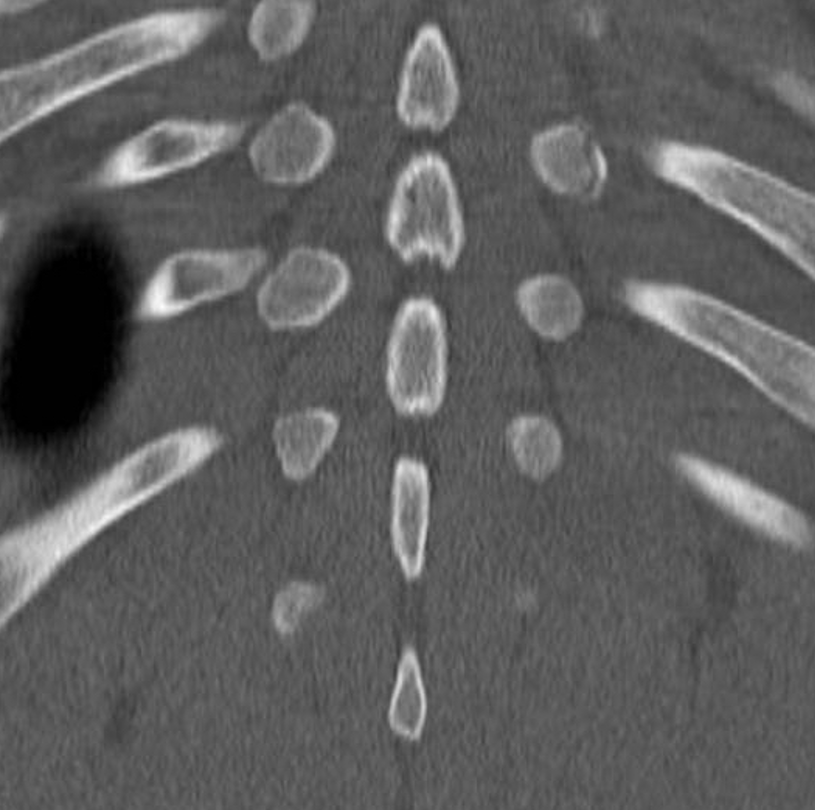

Young gentleman came with severe low back ache following an episode of dengue fever. What do we see here? #spineimaging #medtwitter #radtwitter #FOAMrad #neuroimaging @drvenkimdrd

DrYevSam_Rad's tweet image. Young gentleman came with severe low back ache following an episode of dengue fever. What do we see here?